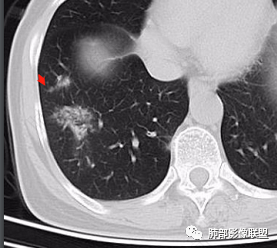

2、CT表现为两肺下叶结节影、斑片影、磨玻璃影,沿支气管血管束分布,部分支气管壁显示增厚。粗略一看部分病灶内似可见“细网格影”,但是仔细观察,可发现此“细网格影”不同于我们常见的“细网格影”,尤其是右肺下叶病灶,可以观察到病灶内部的网格上有高密度结节感或颗粒感,部分层面见“反晕征”,且反晕的边缘亦可观察到结节感。未见胸腔积液。

2、好发部位与其它结核类似,上叶及下叶背段为主。 3、烟花征,反晕征,环呈结节状,可以伴随空洞,树芽征,结节灶,胸水。(反晕征:一般周围实性环形高密度影,中央呈低密度;一般环超过圆的3/4,结核的环主要是小叶核心结节组成,类似于多发树芽征聚集,边缘结节感。中央的晕:可以是腺泡结节,树芽征,细网状,磨玻璃影,很少正常,主要成分是小叶内间质增厚、小叶核心结节、肺泡内病变。)其实也体现了结核的多灶性、多态性特点。